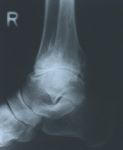

Arthrosebehandlung

Arthrose ist eine Gelenkerkrankung bei der Gelenkknorpel und die Gelenkschmierung nicht mehr

oder nur noch zum Teil vorhanden sind. Dieses bewirkt das die Gelenkflächen aufeinander reiben

und sich daraus Schmerzen und Entzündungen ergeben. Diese Schmerzen sind von unauffällig bis

zu sehr stark je nach Patient vorhanden. Die daraus resultierende Schonhaltung ist eine Fehlhaltung

die wiederum andere Schmerzen bedingt. Es gibt verschiedene Arten der Arthrosen: